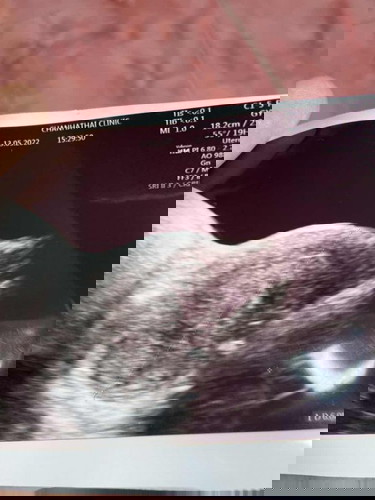

คุณแม่ท้องกี่สัปดาห์ถือเห็นเป็นถุงครรภ์ หรือเห็นลูกคะ เราเพิ่งตรวจเจอ2ขีดนับแล้ว 5สัปดาห์ ซาวด์ยังไม่เจอแม้แต่ถุงครรภ์เลยค่ะ แอบกังวลเล็กน้อย เพราะเคยแท้งไปเมื่อปลายปีที่แล้วค่ะ #ขอบคุณล่วงหน้านะคะ #คุณแม่ๆช่วยแนะนำหน่อยค่ะ #ขอบคุณสำหรับคำตอบค่ะ